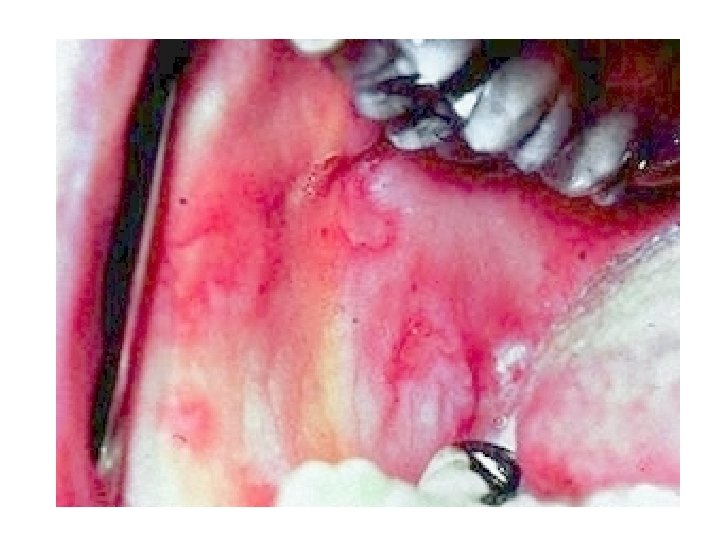

Choice of vehicles for different lesions Lesion Recommended Acute erythema shake lotion, cream Vesicles shake lotion, gel, lotion Blisters Wet dressings, shake lotions Avoided Ointment, paste Paste, ointment, powder Erosions Wet dressings, powder, ointment shake lotion Crusts Ointment, wet dr. Powder, gel Ch. inflammation Ointment

What would you prescribe for: • A burn (with hot water) involving the wrist, with erythema and blisters • A clinical picture with vesicles, yellow ccrusts and oozing erosions • Hyperkeratotic plaque with scales, prominent skin markings and severe pruritus